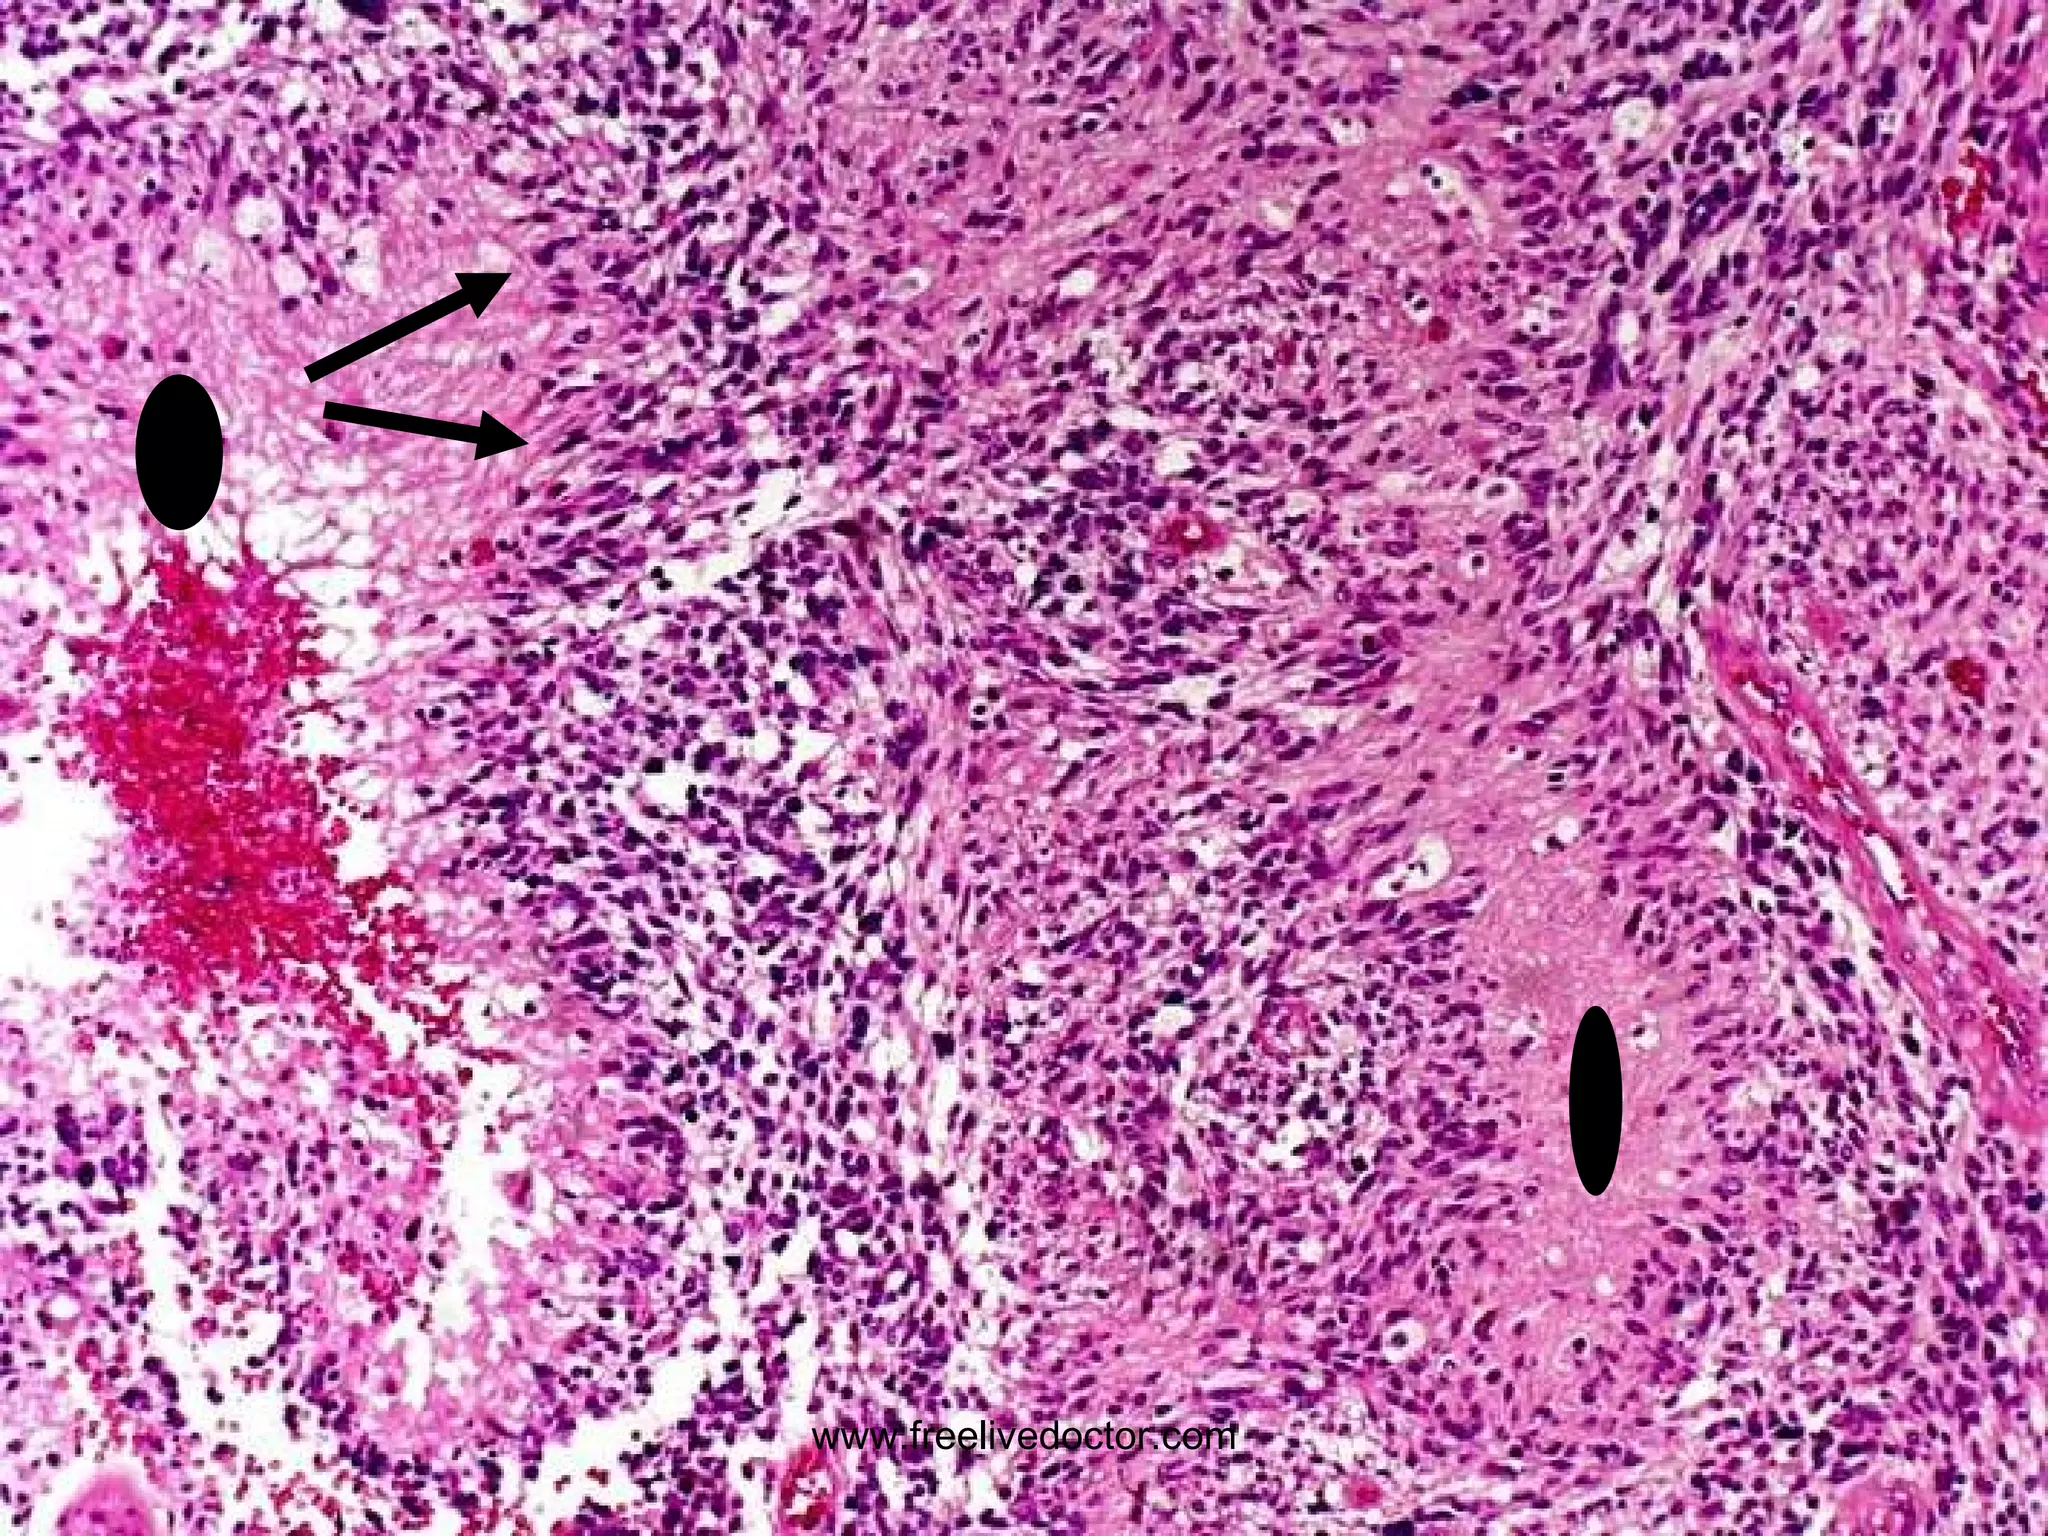

• #155 Glioblastoma (multiforme). Why is it called “multiforme”? Note the 1) palisading (two arrows) and 2) necrosis (ovals) which are hallmarks of GBM.

• #156 Central necrosis is a sign of rapid growth. It outgrows its blood supply.